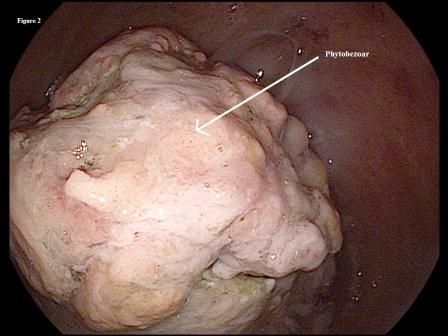

Figure 2.

Laboratory tests revealed the following: hemoglobin 11 g/dL (12-16 g/dL); hematocrit 34% (37%-47%); MCV 82 fL (80.4-95.9 fL); MCH 26 pg/cell (27-31 pg/cell); MCHC 30.2 g/dL (32-36 g/dL); and RDW 14.6% (12%-15%). There were no electrolyte abnormalities, including hypokalemia and a hypochloremic metabolic alkalosis. Abdomen and pelvis CT with contrast revealed that the patient was status post partial gastrectomy. It also showed chronic stable intrahepatic and extrahepatic biliary ductal dilatation and pancreatic duct dilatation with pancreatic atrophy. Upper endoscopy was performed in view of the patient’s history of refractory PUD and multiple abdominal surgeries. It showed a normal gastric remnant, an ulcer at the anastomotic site, and a large bezoar on the gastric side of anastomosis (Figures 1 and 2). Biopsy from the mass showed vegetable fibers, confirming the diagnosis of phytobezoar.